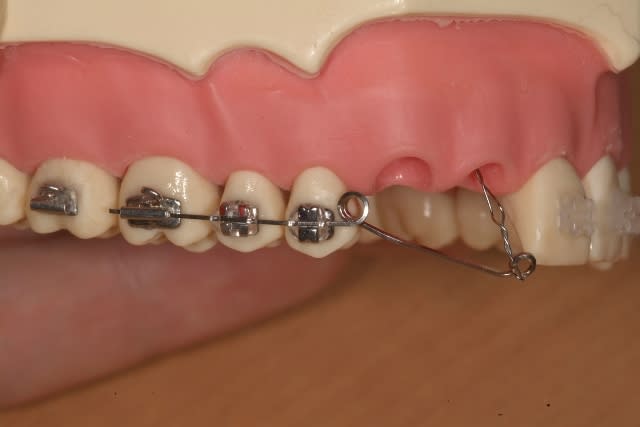

Quant à la mécanique, une fois l'arcade nivelée, je placerais un arc acier 19.25 par exemple, avec un hook serti en mésial de 11 pour avoir une direction de traction assez mésiale, toujours pour le conflit des racines.

Concrètement, le chirurgien maxillo me colle un oeillet sur 13, et y passe une ligature en double qu'il toronne.Il me la fait sortir dans le site d'extraction de 52-53 et je la relie via une ligature élastique au hook.C'est la tension du fil élastique qui détermine la force, mais là, je dois dire que je ne m'en préoccupe pas vraiment puisque de toute facon le réglage avec ce dispositif est malaisé; j'ai peut être tort.

Je serai attentif à la direction selon laquelle la 13 évolue, pour réajustement si nécessaire, mais il me semble que de cette façon, cette canine se redressera et descendra en même temps, 14 et 15 étant elles même descendues entre temps.

Le centre de résistance de 13 n'est pas aussi apical que pour une dent à apex fermé et si le chirurgien dégage ce qu'il faut d'os (mais pas à la dynamite) je le sens bien.

Le seul point qui me chagrine est le manque apparent de contrôle de la force de traction et de son amplitude. N’est-ce pas important ? Depuis le temps qu’on parle des forces légères (plus de 30 ans, je rappelle qu’on n’a pas attendu Damon pour cela), ne pourrais-tu pas essayer d’imaginer un système qui délivre une force légère et constante et qui permette ce contrôle ?

Pour les forces douces, si tu trouves que mon système ne permet pas un contrôle suffisant du module de la force, alors je peux ne pas faire la traction avec une ligature élastique sur l'arc acier, mais ajouter un arc NiTi sur mon arc acier tenu par des bi-level pins (TP orthodontics ;j'utilise des Bk avec slot vertical), et je tracte 13 sur cet arc niti avec un petit v dedans( pourla ligature métalique cette fois) pour garder une direction de traction mésiale.

La mécanique que tu proposes est remarquablement bien pensée, cependant je regrette son manque d’amplitude. Et tu n’amélioreras pas celle-ci en employant des « bi-level pins », au contraire, car le fil NiTi sera alors encore plus proche de l’émergence de ligature. Tu devras alors multiplier les activations..

Ne peux-tu imaginer un ressort de type cantilever qui délivre une force légère, contrôlée et d’une plus grande amplitude. ?

Voilà une alternative avec un dispositif qui permet le réglage de la force en module et direction. Je l'utiliserais avec un double tube sur 16 , avec le ressort dans le tube gingival et un arc complet dans l'autre.

Effets indésirables : extrusion et mésioversion coronaire de 16 mais vu la force, négligeable a à mon avis( mini vis si doutes). Si tu ne veux pas engager la 14, le ressort prendrait 16 et 15.

L'espace entre 14 et 11 est plus reduit chez ton patient que sur mon modèle.

Avec la première solution dont j'avais parlé précédement, je mets un up-righting-spring(TP ortho) pour envoyer la racine de 14 en distal.

le ressort dont tu parles s'appelle un descendeur canin. A mon avis, et du point de vu biomecanique, l'attacher sur la 4 ou sur la 5 va engendrer une force reactionnelle d'ingression de la premolaire. Donc il faut mieux avoir un double tube sur la molaire, passer un fil rigide dans le tube occlusal sans engager la 4, si l'on veut la laisser libre, et dans le tube gimgival on fait passer le ressort. Ceci donne un brs de levier plus long et plus efficace, et la 6 stabilisee n'aura pas de mouvement parasite. On peut utiliser un dispositif palatin type ATP pour renforcer l'ancrage de la molaire et on peut faire le ressort en TMA .016 X .022 pour plus de souplesse. Le reste tout va bien.